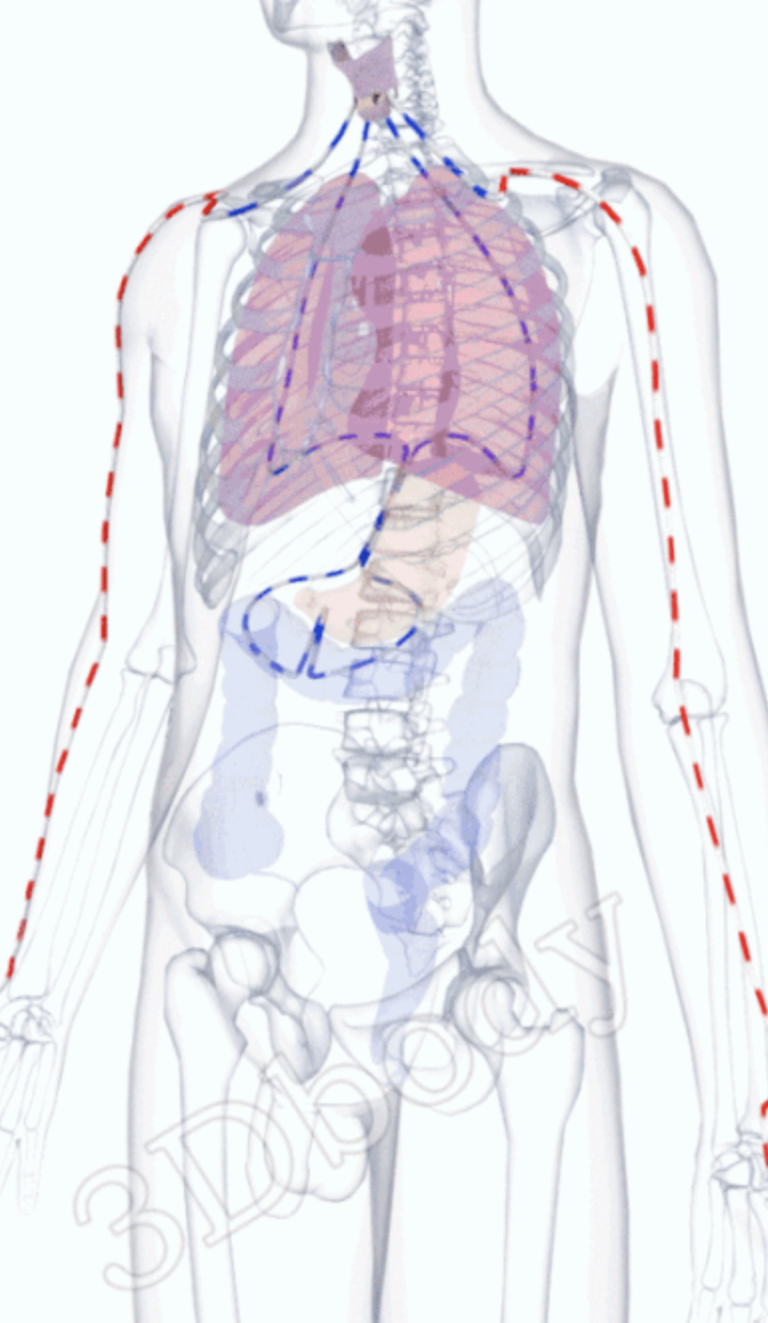

おもに肺の経絡が邪気•ウイルスでダメージを受け、瘀血になって後遺症が残っていると考えます。

また肺と関係が深い脾の経絡は舌に分布し、味覚を司っています。

肺は鼻に開竅して、陽明経の流注は鼻を流れています。

全身治療で五臓六腑の気血を促し、身体全体を回復させ免疫力を取り戻します。